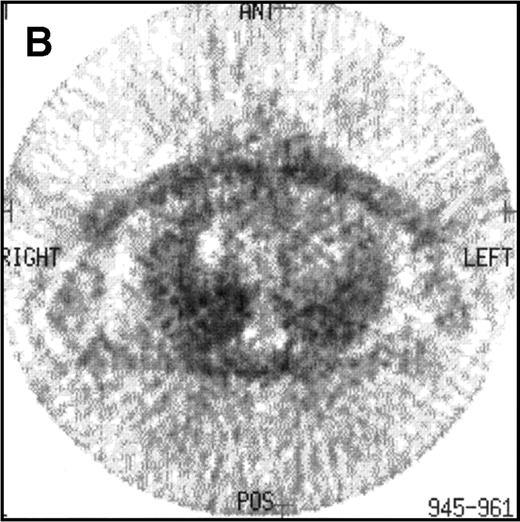

CT and 18F-FDG PET studies at the end of treatment in a case of relapsed HD remaining in clinical CR after a follow-up of 42 months. (A) The CT study at the end of treatment showed a large residual mediastinal mass. (B) The 18F-FDG PET study of this patient was negative.